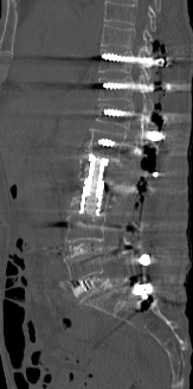

第1腰椎椎体骨折を認めます。MRI検査では圧潰が高度で骨片が後方の神経を圧迫しているのが分かります。強い腰痛、下肢しびれ、不全麻痺により歩けない状態でした。

後方から圧潰した椎体を取り除き神経を除圧して、金属の支柱による椎体置換術を施しました。上下の椎体は骨粗鬆症により脆弱であったため、セメント補強スクリューを使用して引き抜き強度を上げました。固定性が良好なため、術後すぐに離床、歩行訓練を行うことが出来ています。